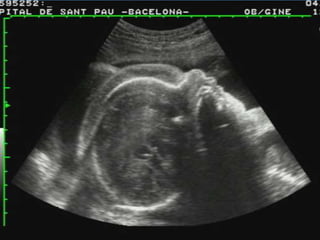

IDIOPÁTICO.

PACIENTE DE 19 AÑOS DE EDAD, III GESTA, II PARA,

FUM: INCIERTA, EMBARAZO ECOGRÁFICO DE 20

SEMANAS + HF.

ESTUDIO CITOGENÉTICO MEDIANTE AMNIOCENTESIS:

CARIOTIPO NORMAL 46 XY.

ECOCARDIOGRAFÍA FETAL NORMAL, VDRL (-), HIV (-).

SE DECIDE CONDUCTA EXPECTANTE, LAS EVALUACIONES

SUCESIVAS NO TUVIERON CAMBIOS.

A LAS 29,3 SEMANAS DESAPARICIÓN DEL HF Y CRECIMIENTO

FETAL EN P50.

A LAS 37 SEMANAS INICIA TRABAJO DE PARTO Y SE OBTIENE

RN NORMAL MASCULINO, PRODUCTO DE PARTO

EUTÓCICO, QUE PESA 2650 G., APGAR 9 PUNTOS.